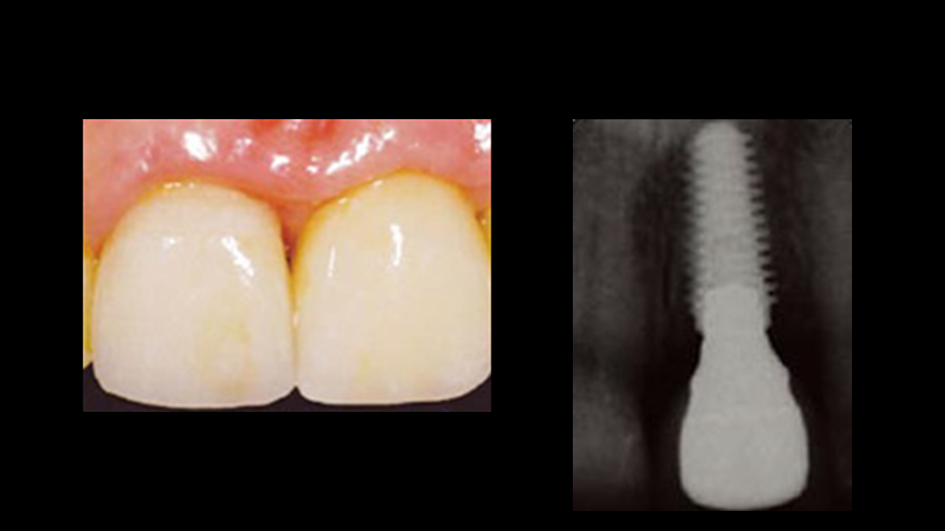

Clinical case: Immediate post-extraction insertion of implant & immediate loading

- Courtesy of Prof. Giuseppe Luongo, Italy -

AnyRidge, immediate loading, single implant, multicenter study, maxillary anterior, Prof. Giuseppe Luongo, single replacement

AnyRidge implant system

Immediate functional loading of single implants: a multicenter study with 4 years of follow-up

/J Dent Res Dent Clin Dent Prospect 2018; 12(1):26-37 | doi: 10.15171/joddd.2018.005

https://www.ncbi.nlm.nih.gov/pubmed/29732018